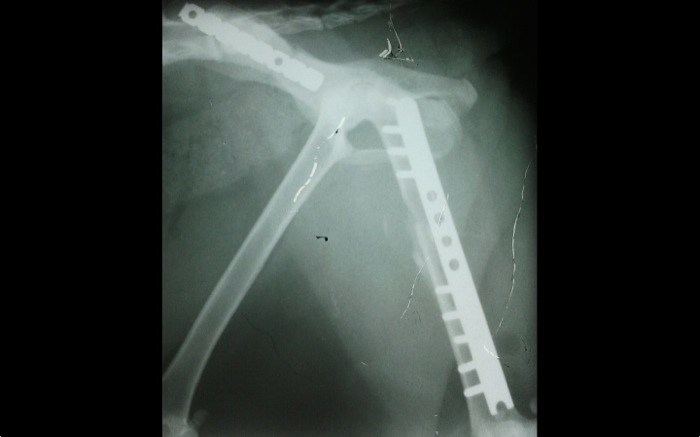

| Pruebas | La imagen radiográfica indica una fractura diafisaria de fémur con varios fragmentos, luxación sacroilícaca del mismo lado y fractura de ileon contralateral. A raíz de ello queda una estenosis secundaria del canal pélvico. |

Proyección ventrodorsal de cadera donde se aprecian las fracturas múltiples de fémur, púbis, isquion y fractura media de ileon con luxación del ileon derecho.

La proyección lateral tampoco nos augura una solución quirúrgica rápida. Se aprecia poco desplazamiento craneal del ileon derecho no fracturado.